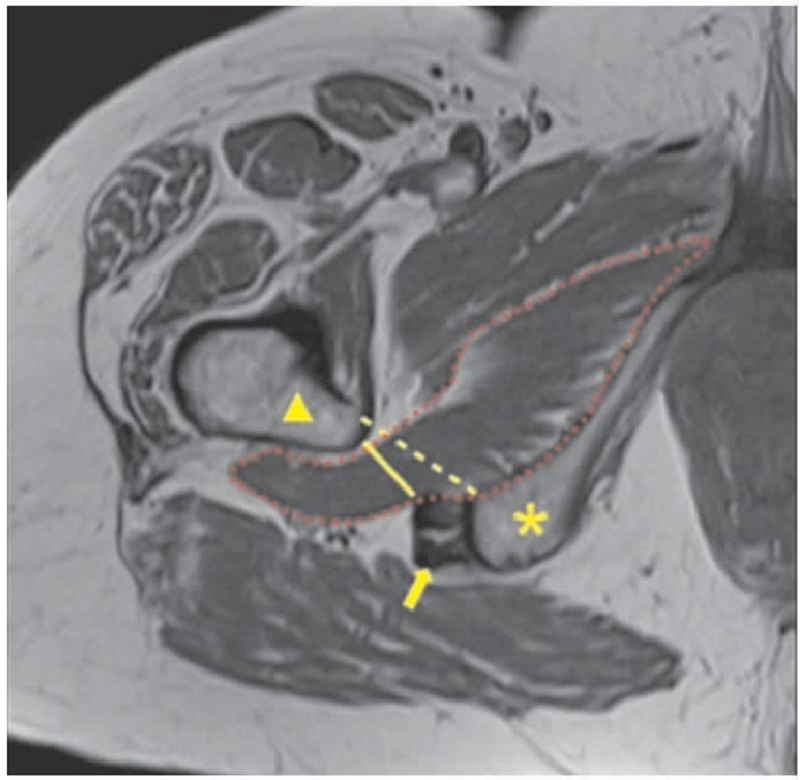

IFI影像学检查中最重要的指标是IFS和QFS(图1),检查可见上述两间隙变窄及股方肌水肿(图2)。IFS和QFS的正常均值分别为25.01mm和15.97mm,IFI患者的IFS和QFS均值分别降至14.91mm和9.57mm。如果以15mm作为IFS阈值,其诊断IFI的准确性可达78.3%;以10mm作为QFS阈值,其诊断IFI的准确性为77.1%。

图1 MRI图像测量IFS和QFS(黄色虚线所示为IFS,黄色实线所示为QFS,星号所示为坐骨结节,三角形所示为小转子,箭头所示为腘绳肌腱,红色虚线所示为股方肌)